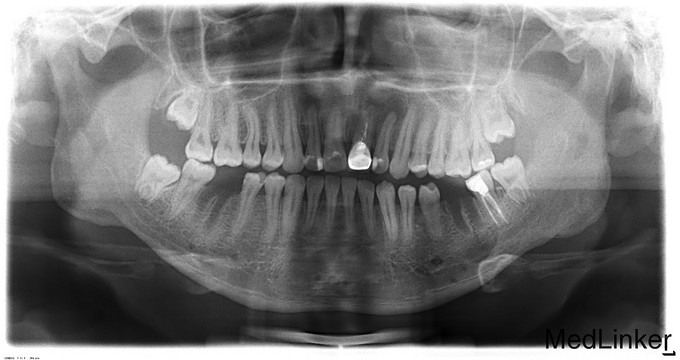

诊断:1.双侧下颌正颌术后钛板存留2.36、46残冠,全麻下行双侧下颌骨钛板取出术+双侧下颌骨邻近瓣转移修复术+36、46拔除术,手术经过顺利,麻醉满意,术后予消炎、消肿等对症治疗。

继续行正畸治疗,术后半年拆钛板的有时候也局麻下完成